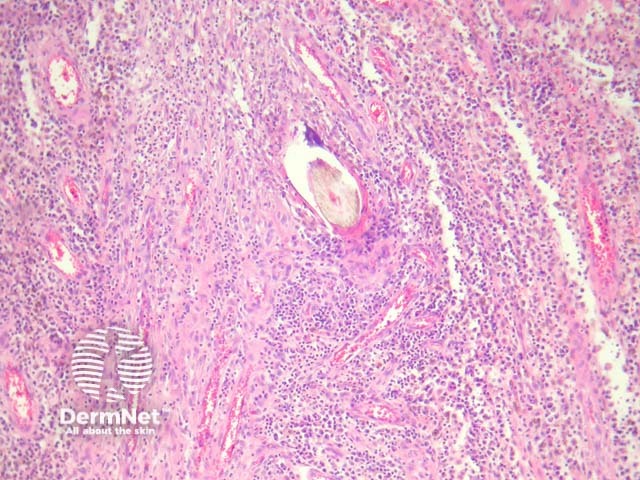

Sections show a dense inflammatory reaction usually occupying the entire dermis with erosion and ulceration of the overlying epidermis (figure 1). Free hair shafts are often seen coursing through the inflammatory focus (figure 2, arrow). Often, the free hair shafts are seen in clusters (figure 3). Dye used to outline the sinus tract for the surgeon may sometimes be seen. Surrounding the free hair shafts is a polymorphous infiltrate which may be rich in plasma cells and lymphocytes (figure 4). Foreign body-type giant cells and neutrophilic abscesses are also commonly observed.

Figure 4